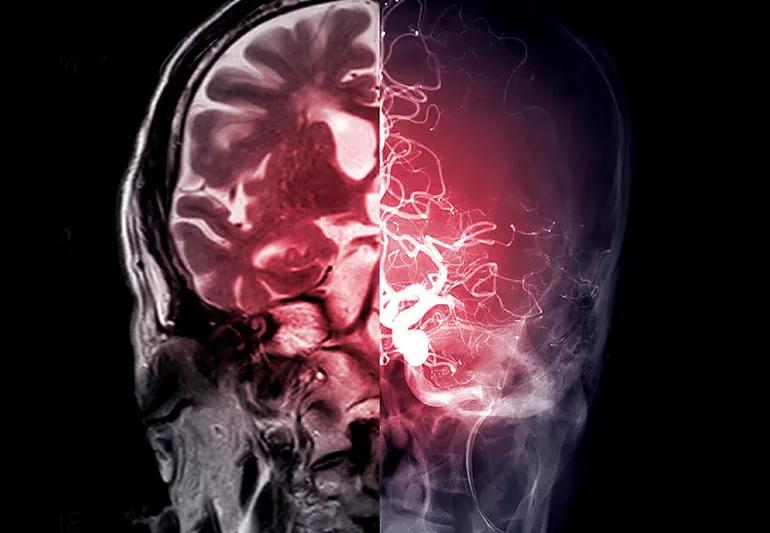

Imaging of a person's brain

When you have a stroke, treatment usually depends on what caused the problem with blood flow to your brain. In some cases, despite an extensive workup, the cause of the stroke may not be evident, or “cryptogenic” (of unknown origin).